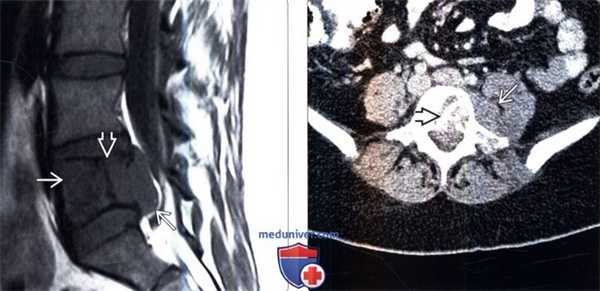

(Слева) Сагиттальный срез, Т1-ВИ: саркома Юинга, практически полностью поражающая тело L5 позвонка и распространяющаяся в эпидуральное пространство. Линия низкой интенсивности сигнала представляет собой не границу опухоли, а зону реактивного склероза. Опухоль в Т1 -режиме характеризуется относительно низкой интенсивностью сигнала по сравнению с красным костным мозгом и мышцами.

(Справа) Аксиальный КТ-срез, этот же пациент: более четко визуализируется зона реактивного остеосклероза в толще опухоли. Видны признаки распространения опухоли в паравертебральные ткани.

(Слева) На сагиттальном Т2-ВИ этого же пациента сигнал опухоли изоинтенсивен сигналу красного костного мозга.

(Справа) На сагиттальном STIR МР-И этого же пациента опухоль характеризуется гиперинтенсивным по сравнению с красным костным мозгом сигналом. В STIR-режиме саркома Юинга обычно видна более четко.